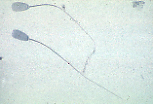

男性生殖系统